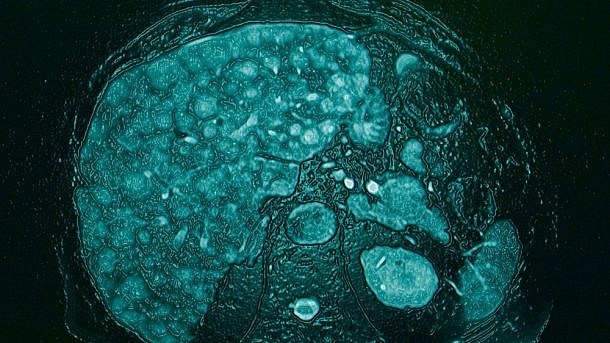

בקרב מטופלים עם שחמת הכבד, התועלת הקלינית של הטיפול באלבומין הומאני עבור מיימת אינה חד משמעית, ואין נתונים זמינים לגבי מצב של מיימת רפרקטורית. במחקר חדש שנערך ב-University of Padova באיטליה והתפרסם בכתב העת Liver International, ביקשו החוקרים להעריך את ההשפעה של מתן ארוך-טווח של אלבומין על אשפוזים דחופים ותמותה בקרב מטופלים עם שחמת ומיימת רפרקטורית.